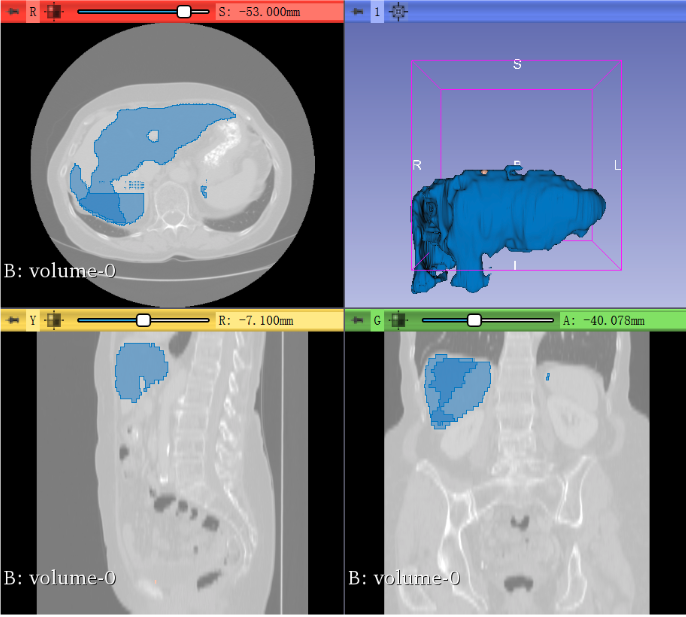

这样我们就得到了自动分割好的模型: